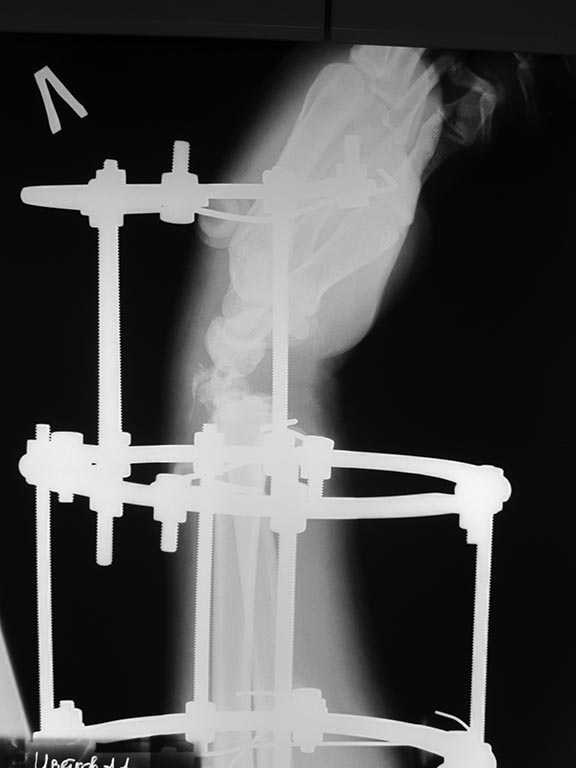

Рентгенограммы:

Здравствуйте! Кисть в подвывихе к тылу. Возможно стоит вставить в дистальное кольцо шарниры или вставки, для того, чтобы тракцию осуществлять под углом, т.е. в ладонную сторону. Пример аппарата во вложении, только тут тракция в другую сторону - к тылу, а вам надо в ладонную.

Приветствую! Учитывая многооскольчатый характер перелома (тип С) и открытый характер перелома конечно АВФ, только нужны шарниры на дистальное кольцо и локтевая девиация

Это классический переломо-вывих в лучезапястном суставе, выделенный АО в отдельную подгруппы - 23-В2.3. В свежем случае здесь показано закрытое вправление и наружная фиксация повязками или аппаратом, в качестве окончательного метода для предотвращения нестабильности сустава рекомендуется восстановление капсулы сустава, в первую очередь тыльной - т.е. репозиция и фиксация всех этих мелких фрагментов, послеоперационная иммобилизация аппаратом внешней фиксации